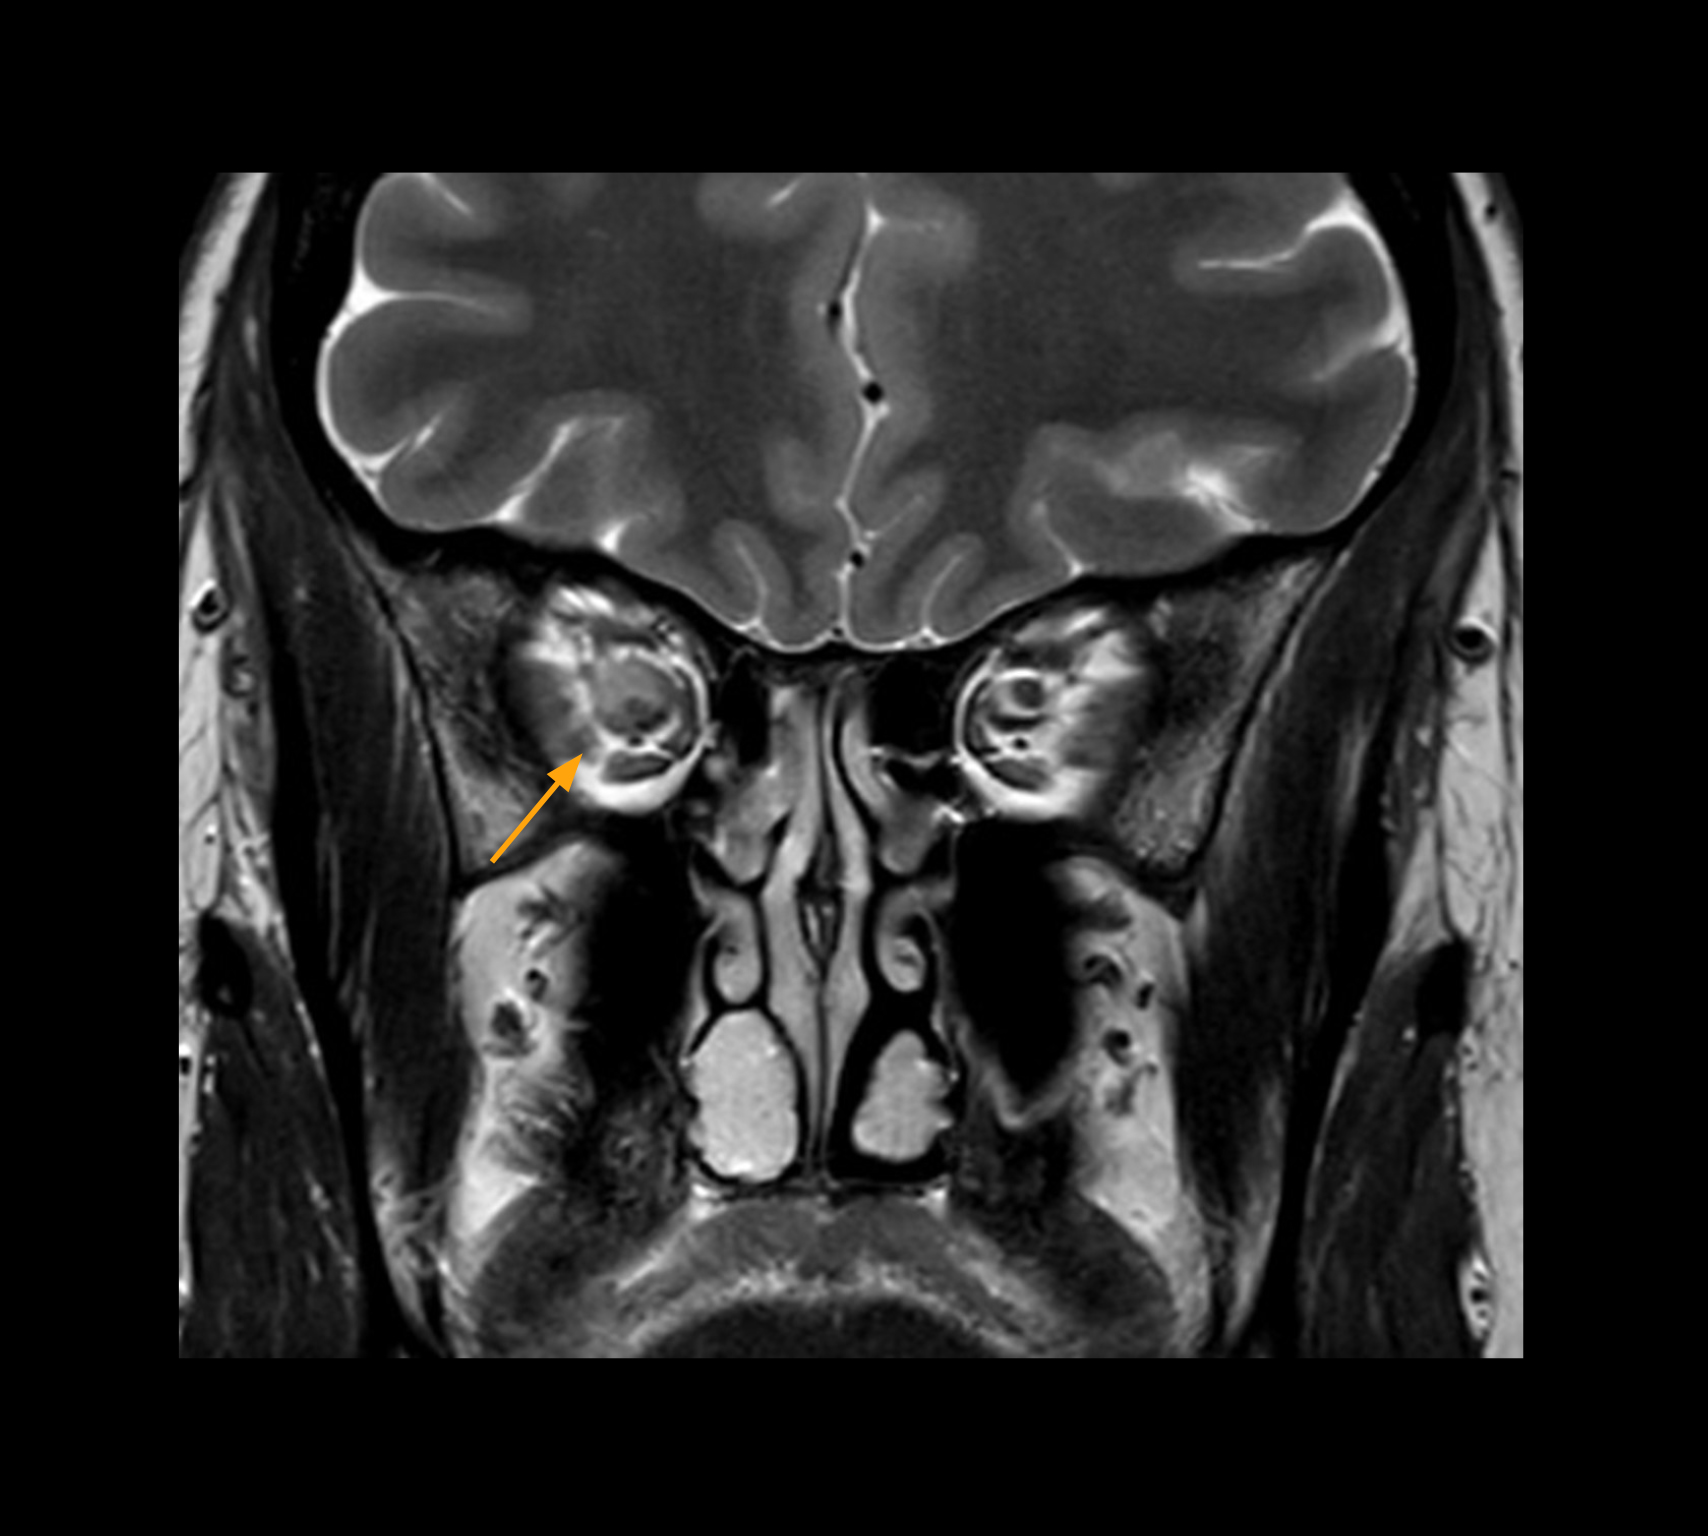

In select cases, the MR 7700 has helped the hospital’s physicians more clearly visualize pathology. “We’re definitely getting the impression that tumors are better delineated with the MR7700,” Dr. Heindel says. “For example, I examined a patient who had been diagnosed in another hospital with possible neuritis of the optic nerve. However, the MR 7700 images allowed me to diagnose it as an optic nerve sheath meningioma, a rare and often misdiagnosed, slowly growing tumor that wascausing the visual disturbances in the patient. The lesion was so well delineated on the high resolution MR 7700 images that our neurosurgeon decided he did not need a biopsy before proceeding directly with decompression of the optic canal and peeling away those tumor cells.”

High-resolution MRI impressively demonstrates the compression and narrowing of the right optic nerve in this case of optic nerve sheath meningioma (ONSM). The coronal T2-weighted images show the hyper-intense, half-moon shaped lesion, that is clearly visible in the axial T1W image after contrast injection (right). These imaging findings were so convincing that there sponsible neurosurgeon did not consider a pretherapeutic histological clarification.

High resolution-MRI impressively demonstrates the compression and narrowing of the right optic nerve in this case of optic nerve sheath meningioma (ONSM). The coronal T2-weighted images show the hyper-intense, half-moon shaped lesion, that is clearly visible in the axial T1W image after contrast injection (right). These imaging findings were so convincing that there sponsible neurosurgeon did not consider a pretherapeutic histological clarification.